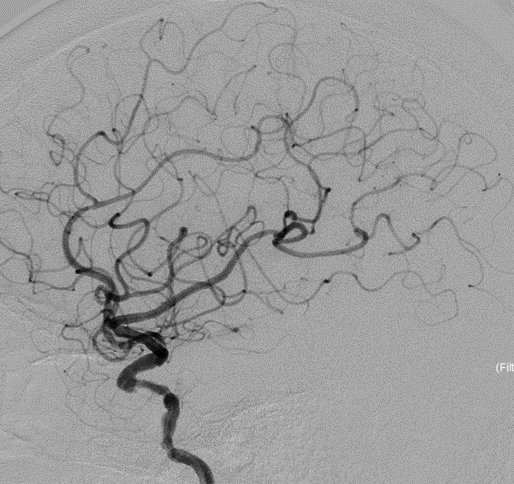

右侧颈动脉造影

左侧颈动脉造影